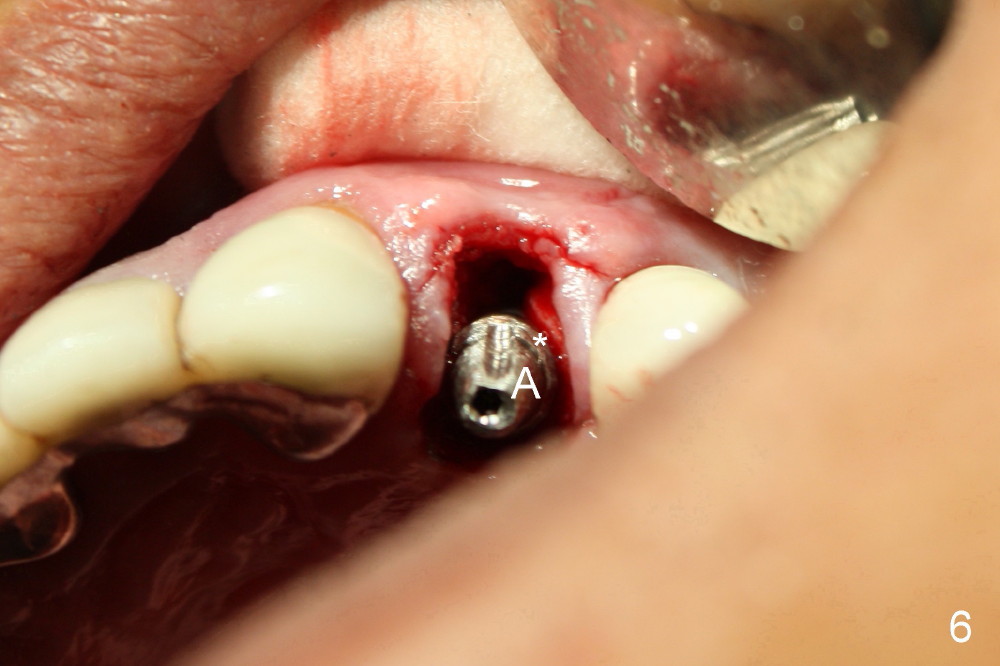

A 50-year-old man has mild pain in the upper left 1st bicuspid 3 years after root canal retreatment with placement of two posts (Fig.1). Findings of clinical exam are consistent with root fracture (Fig.2). Extraction reveals two fused roots (Fig.3,4). Probing indicates that the buccal plate is defective. Osteotomy is initiated in the palatal socket with a 2 mm pilot drill, followed by 2.5 and 3.0 mm reamers and 4.5x20 mm tap. The septum appears to have been pushed buccally (Fig.5 *) and form a new buccal wall (partially, strengthened by bone graft mentioned below) for the implant to be placed. The implant (4.5x20 mm) is placed in the palatal socket (Fig.6 *) with insertion of an abutment (A: 3.5x5 mm 0º), while a mixture of autogenous bone (harvested from reamers) and Synthograft (Bicon) is placed in the shrunken buccal socket (Fig.7; using allograft may decrease postop bony shrinkage). The bone graft is then contained by an immediate provisonal without collagen membrane or flaps. The patient is doing well postop. The gingiva is healthy (Fig.8*) when the provisional is removed 3 months postop with normal papillae (Fig.9 arrowheads). It remains the same 1 month post cementation (Fig.10,11). For further follow up, see immediate implant of the tooth #13.